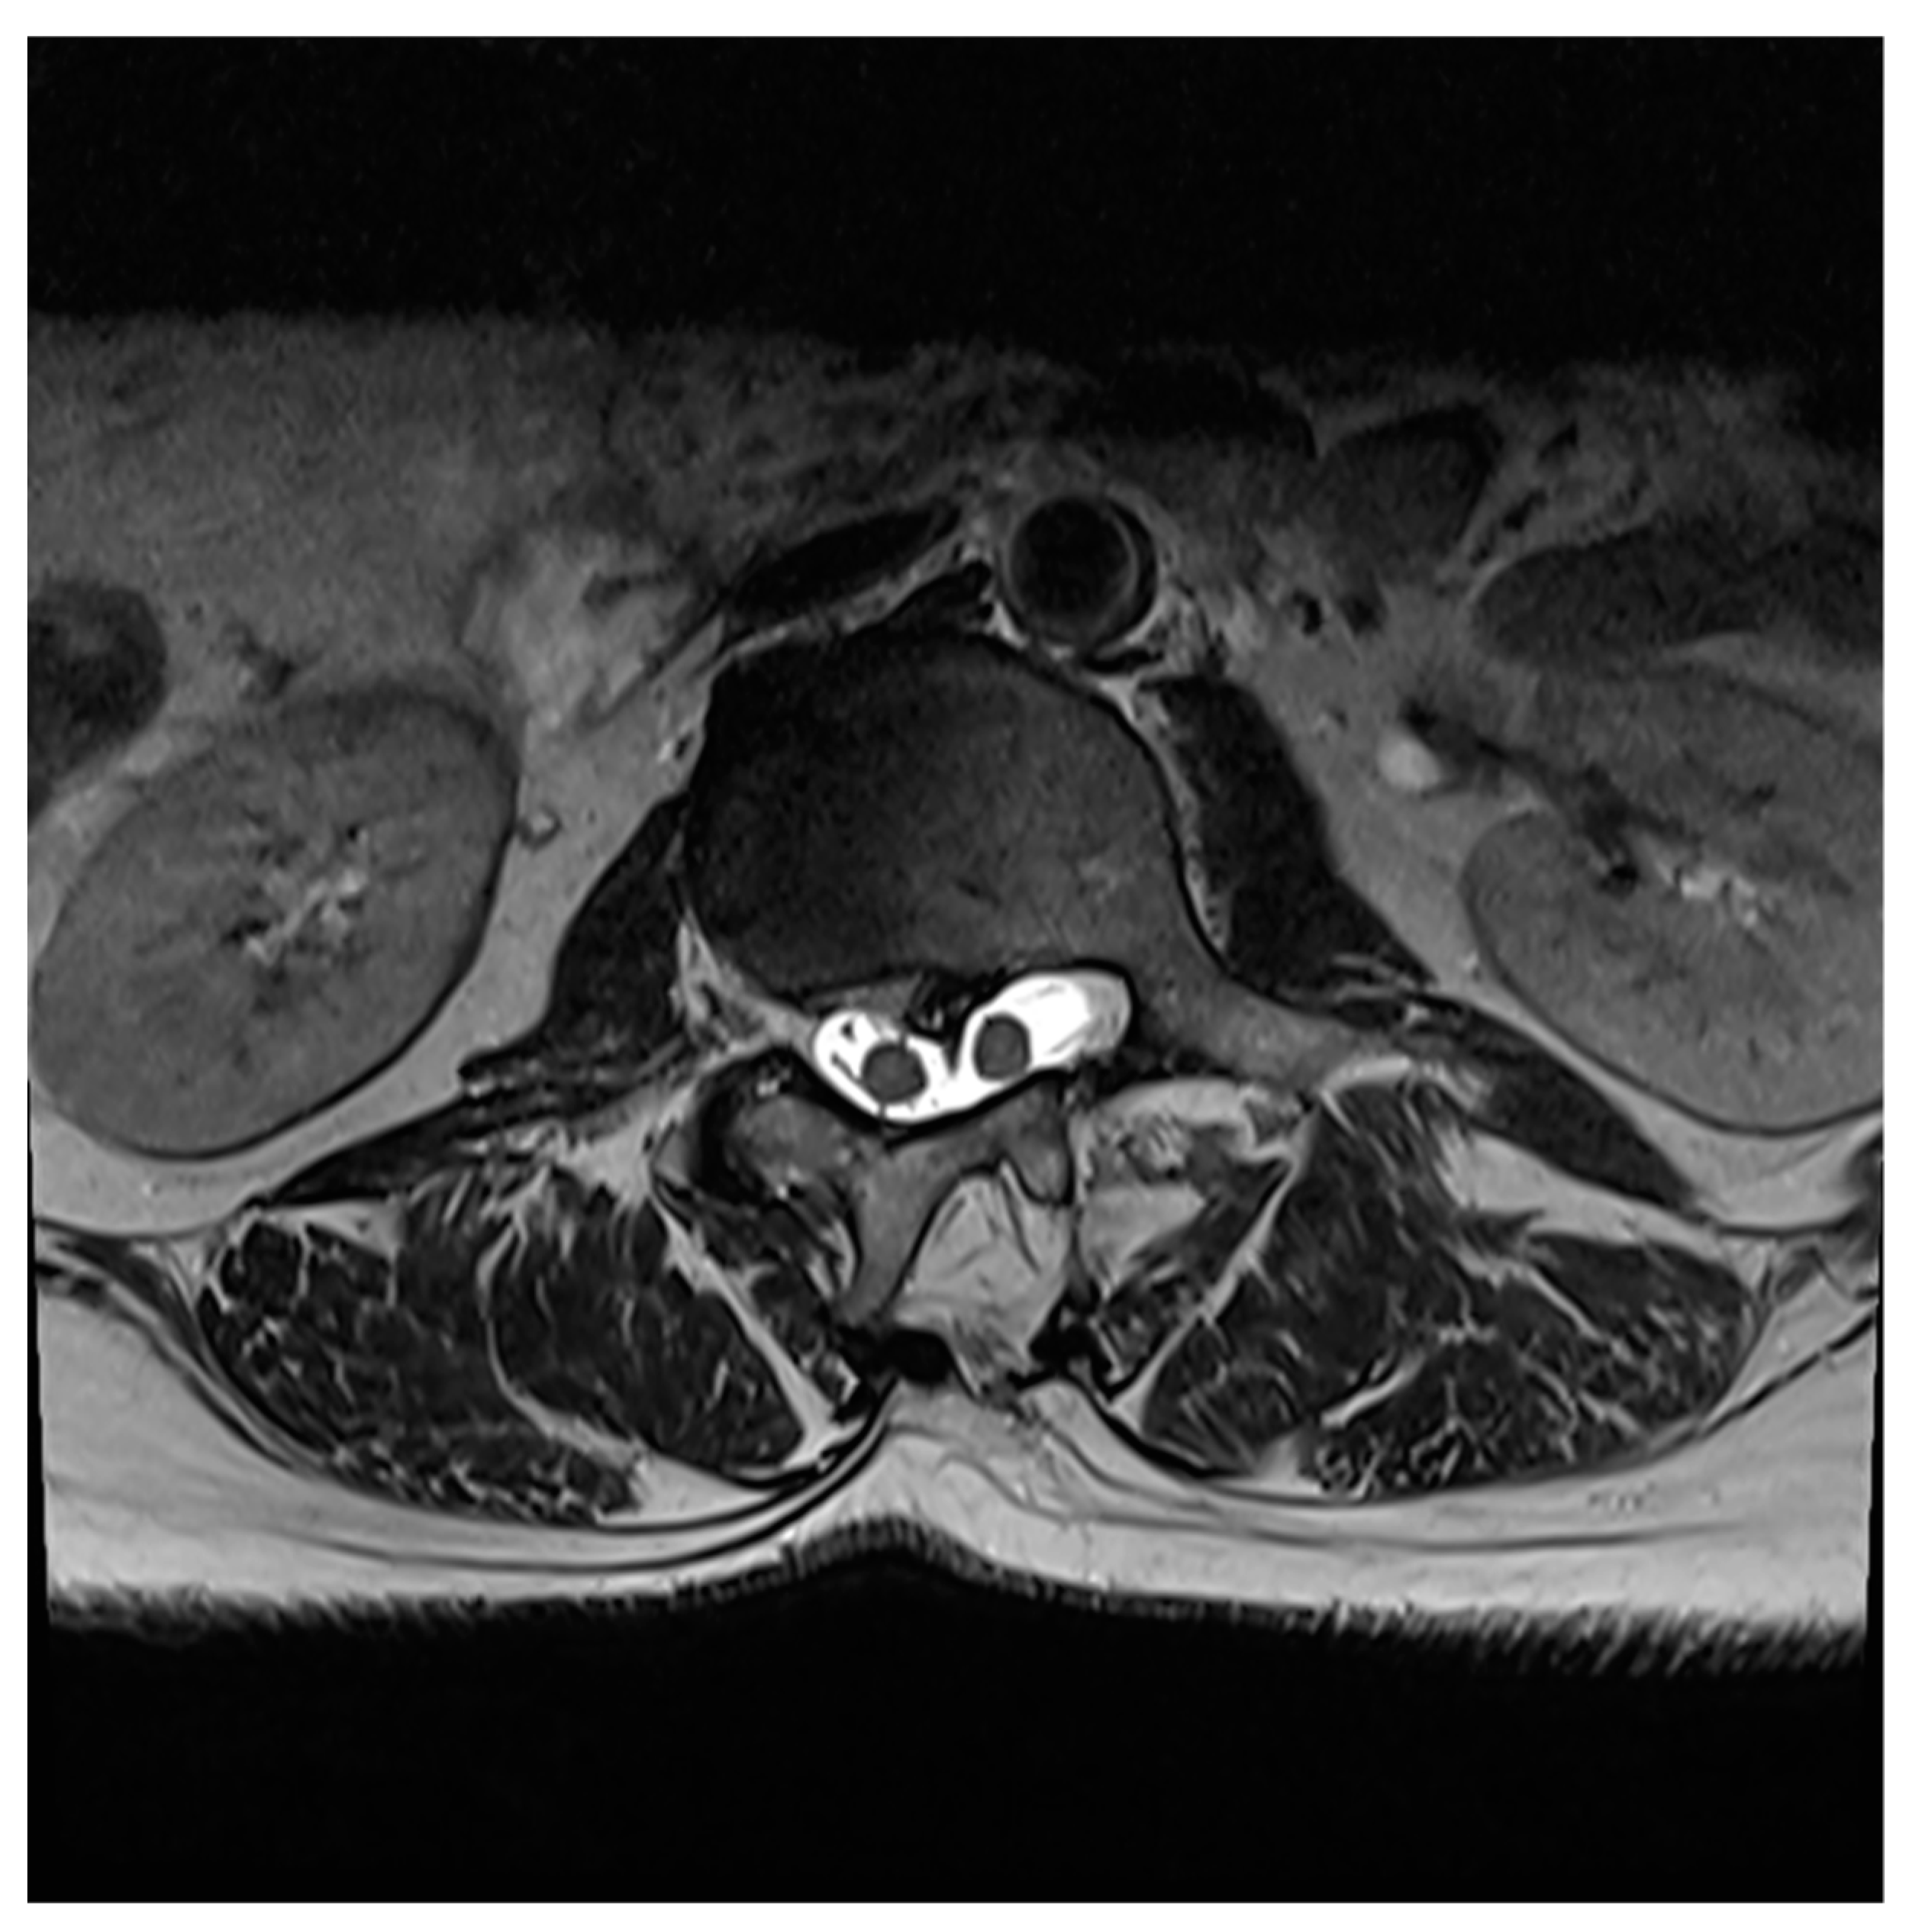

Figure 2. Axial T2WI image showing Dual hemi cord within two dural sac separated by intervening bony septum(Type i diastematomyelia).

Diastematomyelia can be classified into two, depending upon the separation of dura (6):

I.

Double dural sacs with common midline spur- symptomatic and more severe